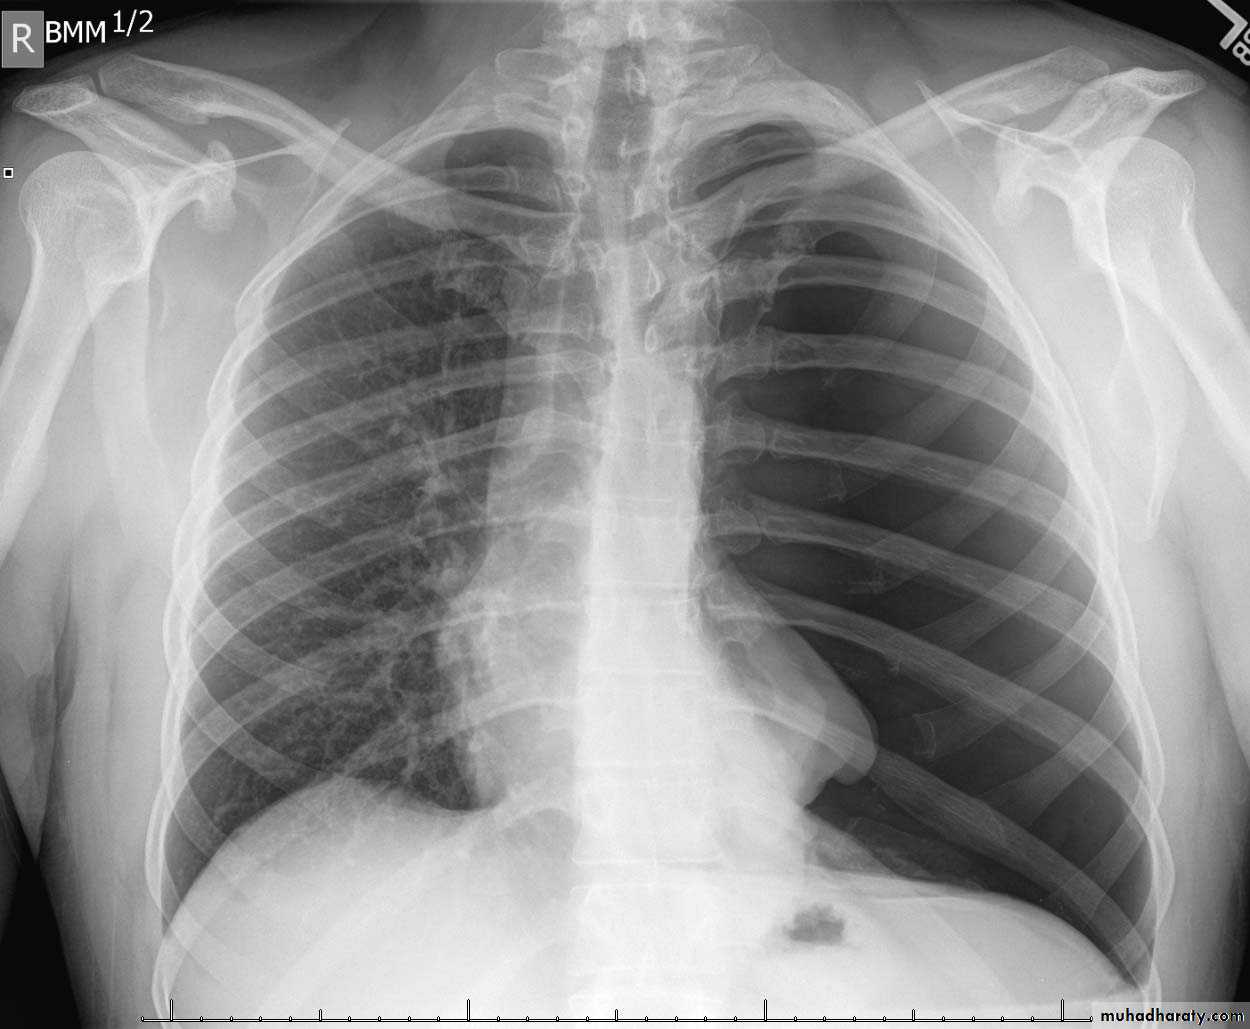

48.opasified hemi thorax

49.total collapse

Total collapse total consolidation

Total collapse